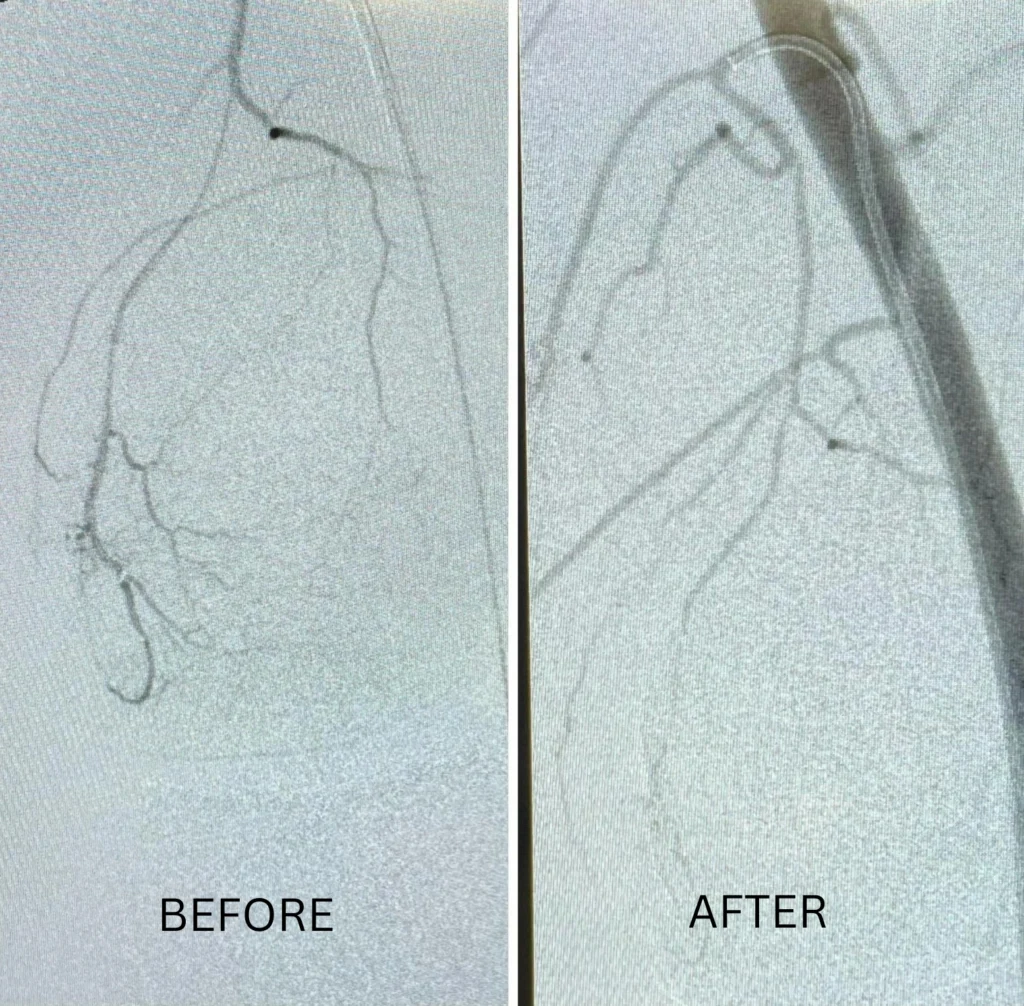

MSK embolization is performed through a small puncture in the wrist or groin, without any surgical incision. Using real-time imaging guidance, a thin catheter is navigated to the abnormal blood vessels supplying the inflamed area. Tiny embolic particles are then delivered to reduce abnormal blood flow and inflammation.